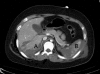

Investigation of blunt abdominal trauma